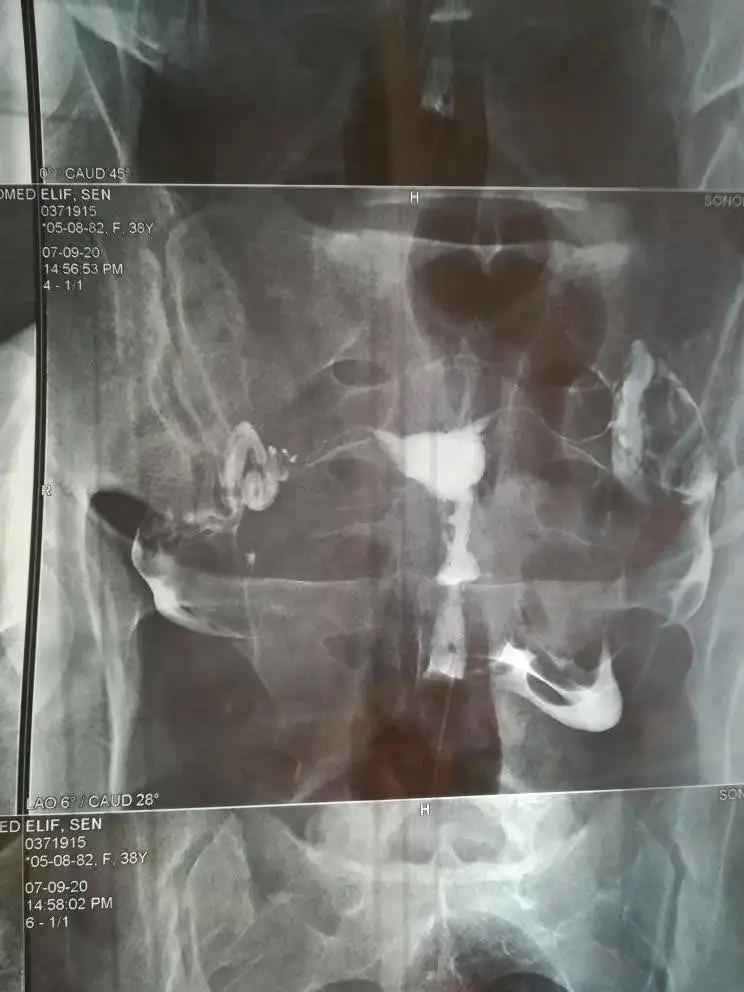

Benim hikayem burda detayları okumak istersen. 1 tüp bebk negatifim var 2.ye hazırlanırken hamile kaldım. O arada histereskopi olmuştum. Rahim filmim ilk sayfada bak bakınca anlarsın sen de zaten. Filmime bakan bir ton doktor oldu aralarında prof da dahil. Herkes normal dedi. Tüp bebek doktorum Eray Çalışkan'dı. O dedi bak rahminde bir problem var bu yüzde elli düşüğe sebep olur. Genelde 2 düşük sonrası histereskopi ila düzeltilir dedi. Tam redaviye başlayacağımız gün öğrendik. Bir şey diyemedik. Allah'a emanet dedik başladık. Bende amh düşük. Tek embriyom oldu transfer oldu. O da negatif sonuçlandı. Ardından hocaya hemen histereskopi istiyoruz biz düşük riskini almak istemiyoruz dedik. Ve rahme atılan çizik gebe kalma ihtimalini arttırdığı için de istiyoruz dedik. O da çok doğru karar dedi keşke herkesr yapsak dedi. Çünkü hsgde görünmeyen perde polip varsa onlar da temizlenecekti. Neyse ki sorun çıkmadı başka tepedeki çıkıntı giderildi. Operasyonumu Bertan Akar yaptı. Özel Kocaeli Hastanesi'nde. Eray hoca o da yapabilir dedi maddi olarak biraz daha uyguna geleceği için onu seçtik bu süreçte maddiyat da düşünmek gerekiyor. Şubatta histereskopi oldum. Mart sonu regl olunca 2. Tüp bebek denememi yapacaktım. Hamile kalmışım.